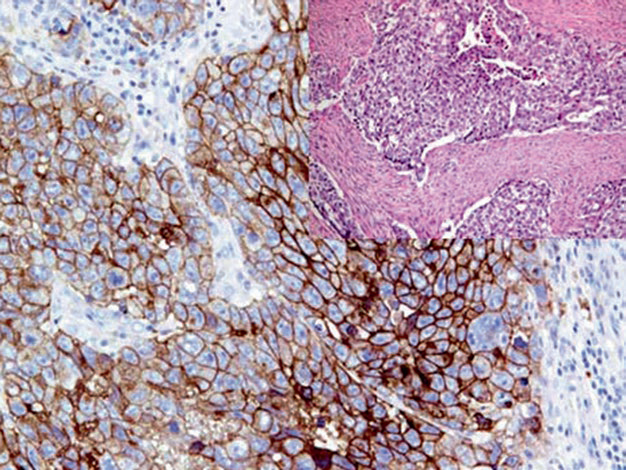

图1. 卵黄囊瘤中,细胞核强阳性表达SALL-4。

具体病例的解读中需要注意,SALL-4不仅表达于生殖细胞肿瘤,还可标语的部分非生殖细胞肿瘤,如卵巢浆液性癌、肺腺癌、胆管癌、尿路上皮癌、小细胞癌。阳性表达模式:细胞核